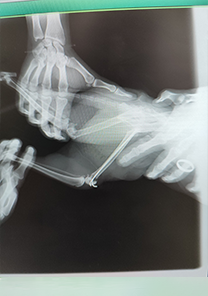

Tayfun Bey'in Kedisi Minnoş

Tayfun Bey'in kedisi Minnoş'un femur distalinde parçalı bir kırık tespit edilmiştir. Operasyon günü itibarıyla MN - HUND&KATT kullanılmıştır. Operasyonun üçüncü gününden itibaren kırıkla ilgili ağrı semptomları tamamen kaybolmuş ve Minnoş rahatlıkla yürümeye başlamıştır. Operasyondan 10 gün sonra kaynamalar başlamış ve remodalizasyona geçmiştir.